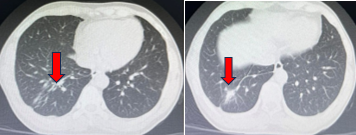

Chụp cộng hưởng từ sọ não 1/10/2019 (sau điều trị)

Hình 5: Các tổn thương não thứ phát biến mất sau xạ phẫu Gamma Knife.

Chụp cộng hưởng từ sọ não sau điều trị ngày 22/6/2020

Hình 11: Không thấy tổn thương thứ phát do di căn

Chụp cộng hưởng từ sọ não sau điều trị ngày 26/10/2021

Hình 12: Không thấy tổn thương thứ phát do di căn.